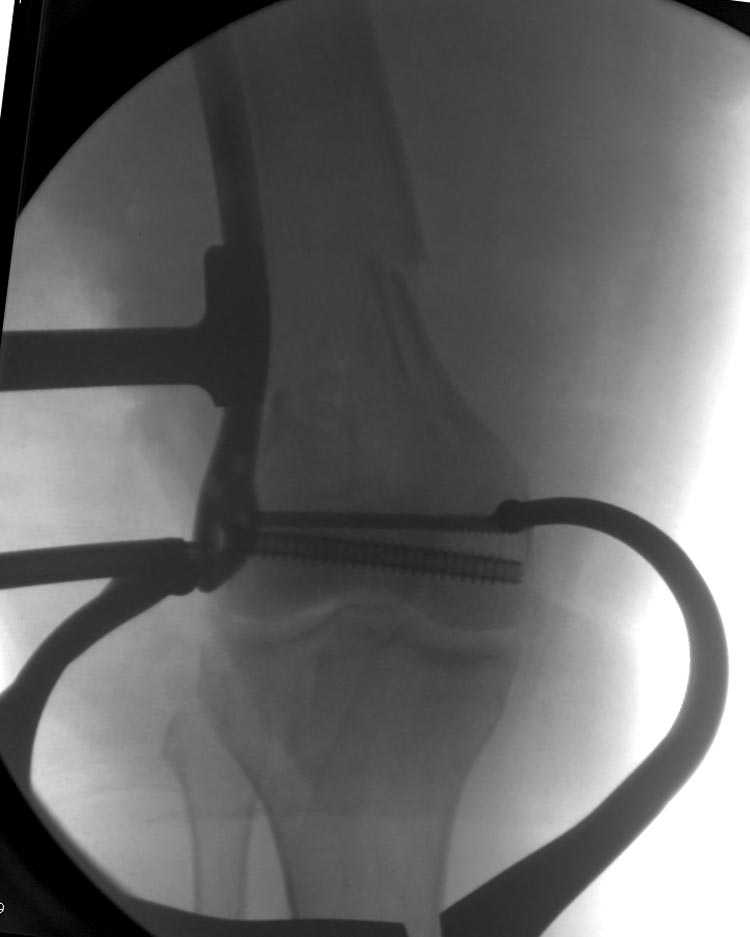

Почти все компании имеют пластины с угловой стабильностью, начиная от Stryker, Zimmer NCB и DePuy Polyaxial Plate . Если у NCB шуруп блокируется специальной шайбой, то Polyaxial Plate имеет вариабельный угол введения шурупов.

Поэтому такие меж и над- мыщелковые переломы более предпочтительным считается фиксировать мыщелковыми пластинами

Устанавливается из малого разреза "не вскрывая сустав" со стороны латерального мыщелка, и Insertion Jig позволяет установить пластину "мостовидно" перкутанно в проксимальном отделе, "не вскрывая и не трогая" место перелома.